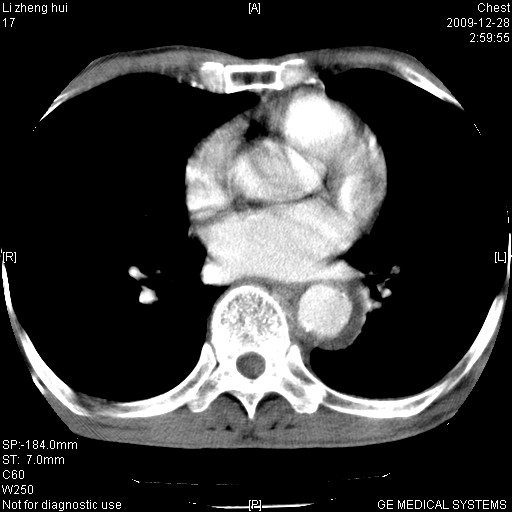

标题: CT23859:胸主动脉瘤 [打印本页]

标题: CT23859:胸主动脉瘤

男  79岁 胸部痛急诊入院,晚上做的增强

考虑主动脉瘤?(增粗、钙化、壁血栓?)

动脉瘤伴附壁血栓

1)考虑胸主动脉壁间血肿或夹层动脉瘤。2)多发性肝囊肿。

1)考虑胸主动脉附壁血栓或夹层动脉瘤。2)多发性肝囊肿。